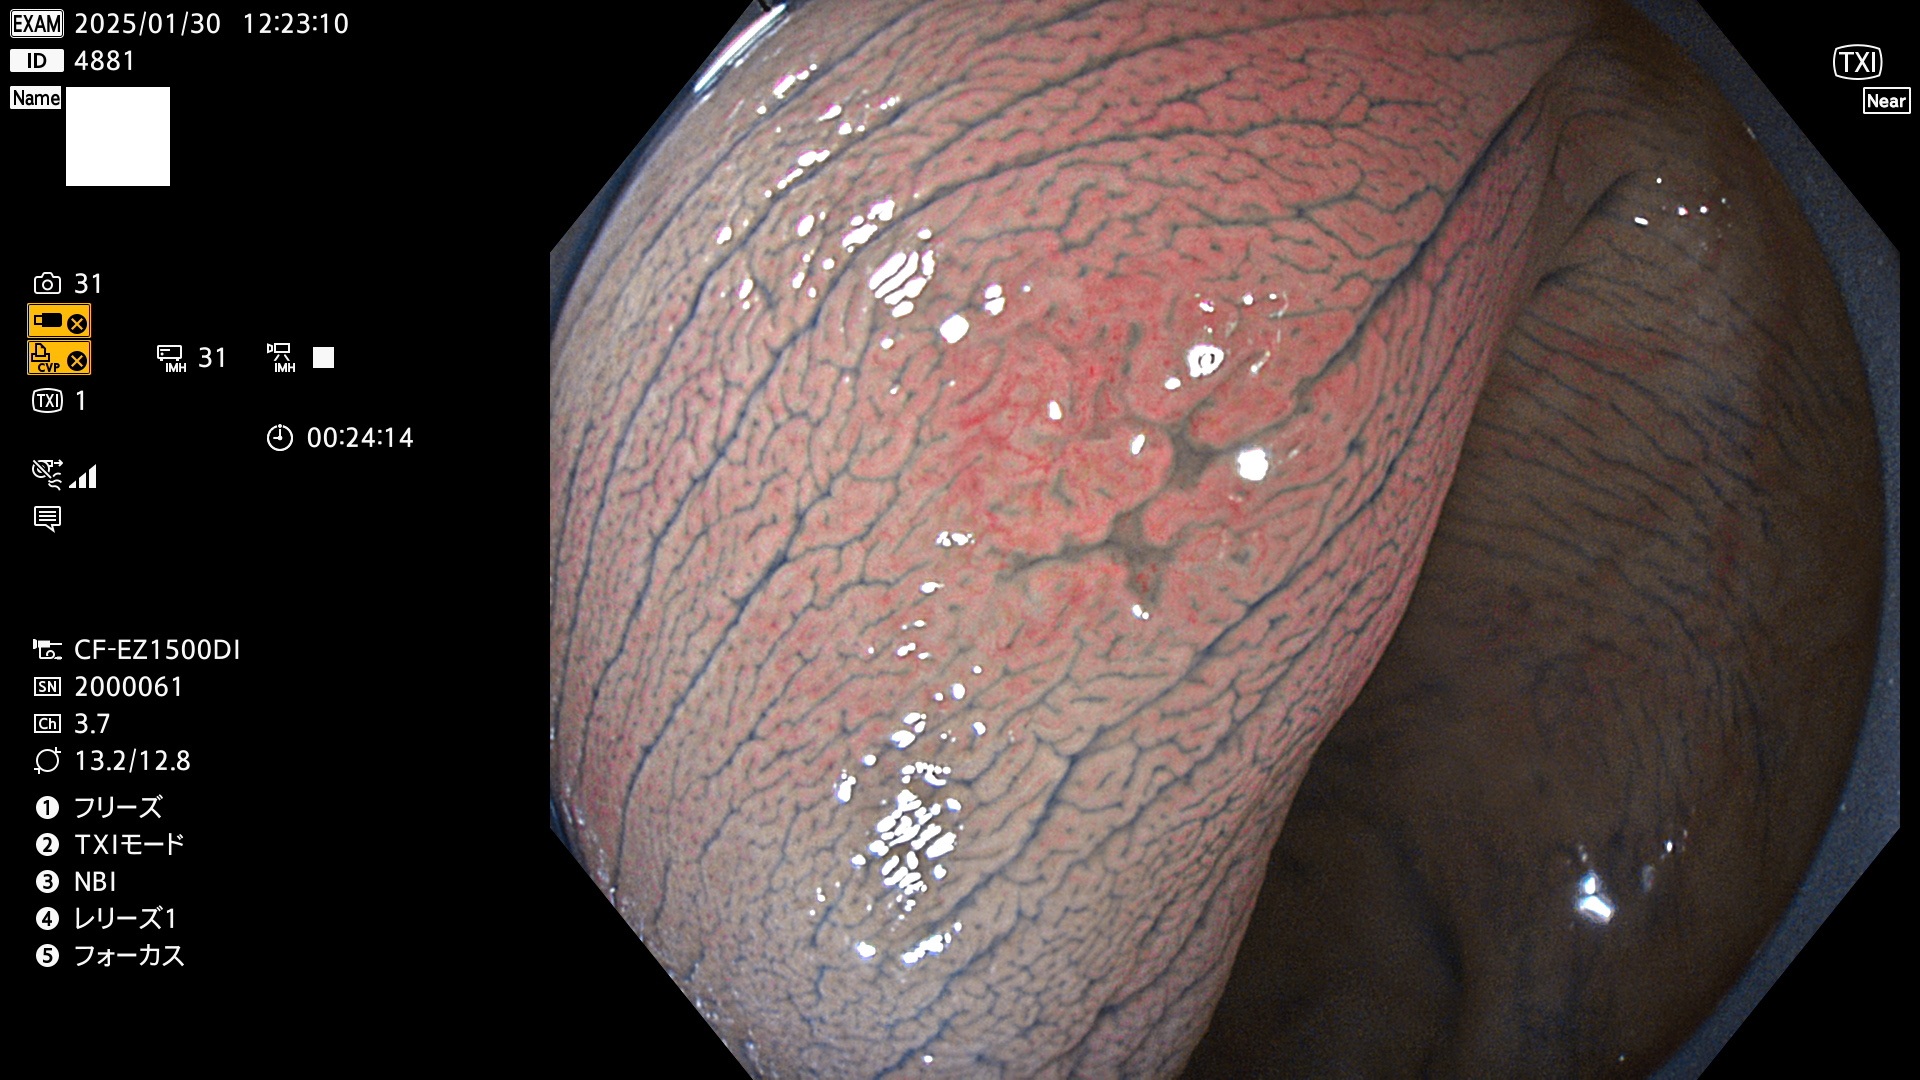

今週のUb、Uc型腺腫

完全に平坦な物をUb、陥凹している物をUcと呼びます。最も発見が難しく危険な病変です。

毎週の検査(木・金・土・日)に発見されたUb、Uc型・腺腫を、その週の日曜の夜にUPし1週間、提示します。

抽出の対象期間 2025年1月23日〜1月26日の4日間(45件の検査)3個 (3/45=6%)